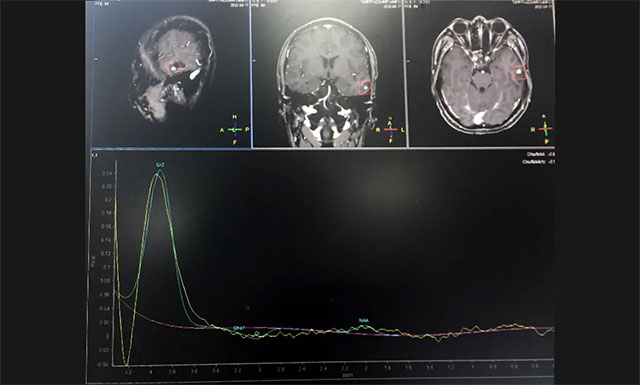

入院后,完善其各项检查,为了更好的手术,并进一步确定病灶位置,增强扫描,进行了头部MRI平扫+增强+MRS+MRSI,影像结果显示:患者左侧颞叶可见一团块状异常信号, T1WI 低信号为主,其内见结节状高信号,T2WI高信号为主,边缘低信号,FLAIR与DWI低信号为主、低混杂信号;MRS示体素位于左侧颞叶病灶,波谱基线不稳。

▲ 患者病灶位于左侧颞叶,其波谱图显示异常